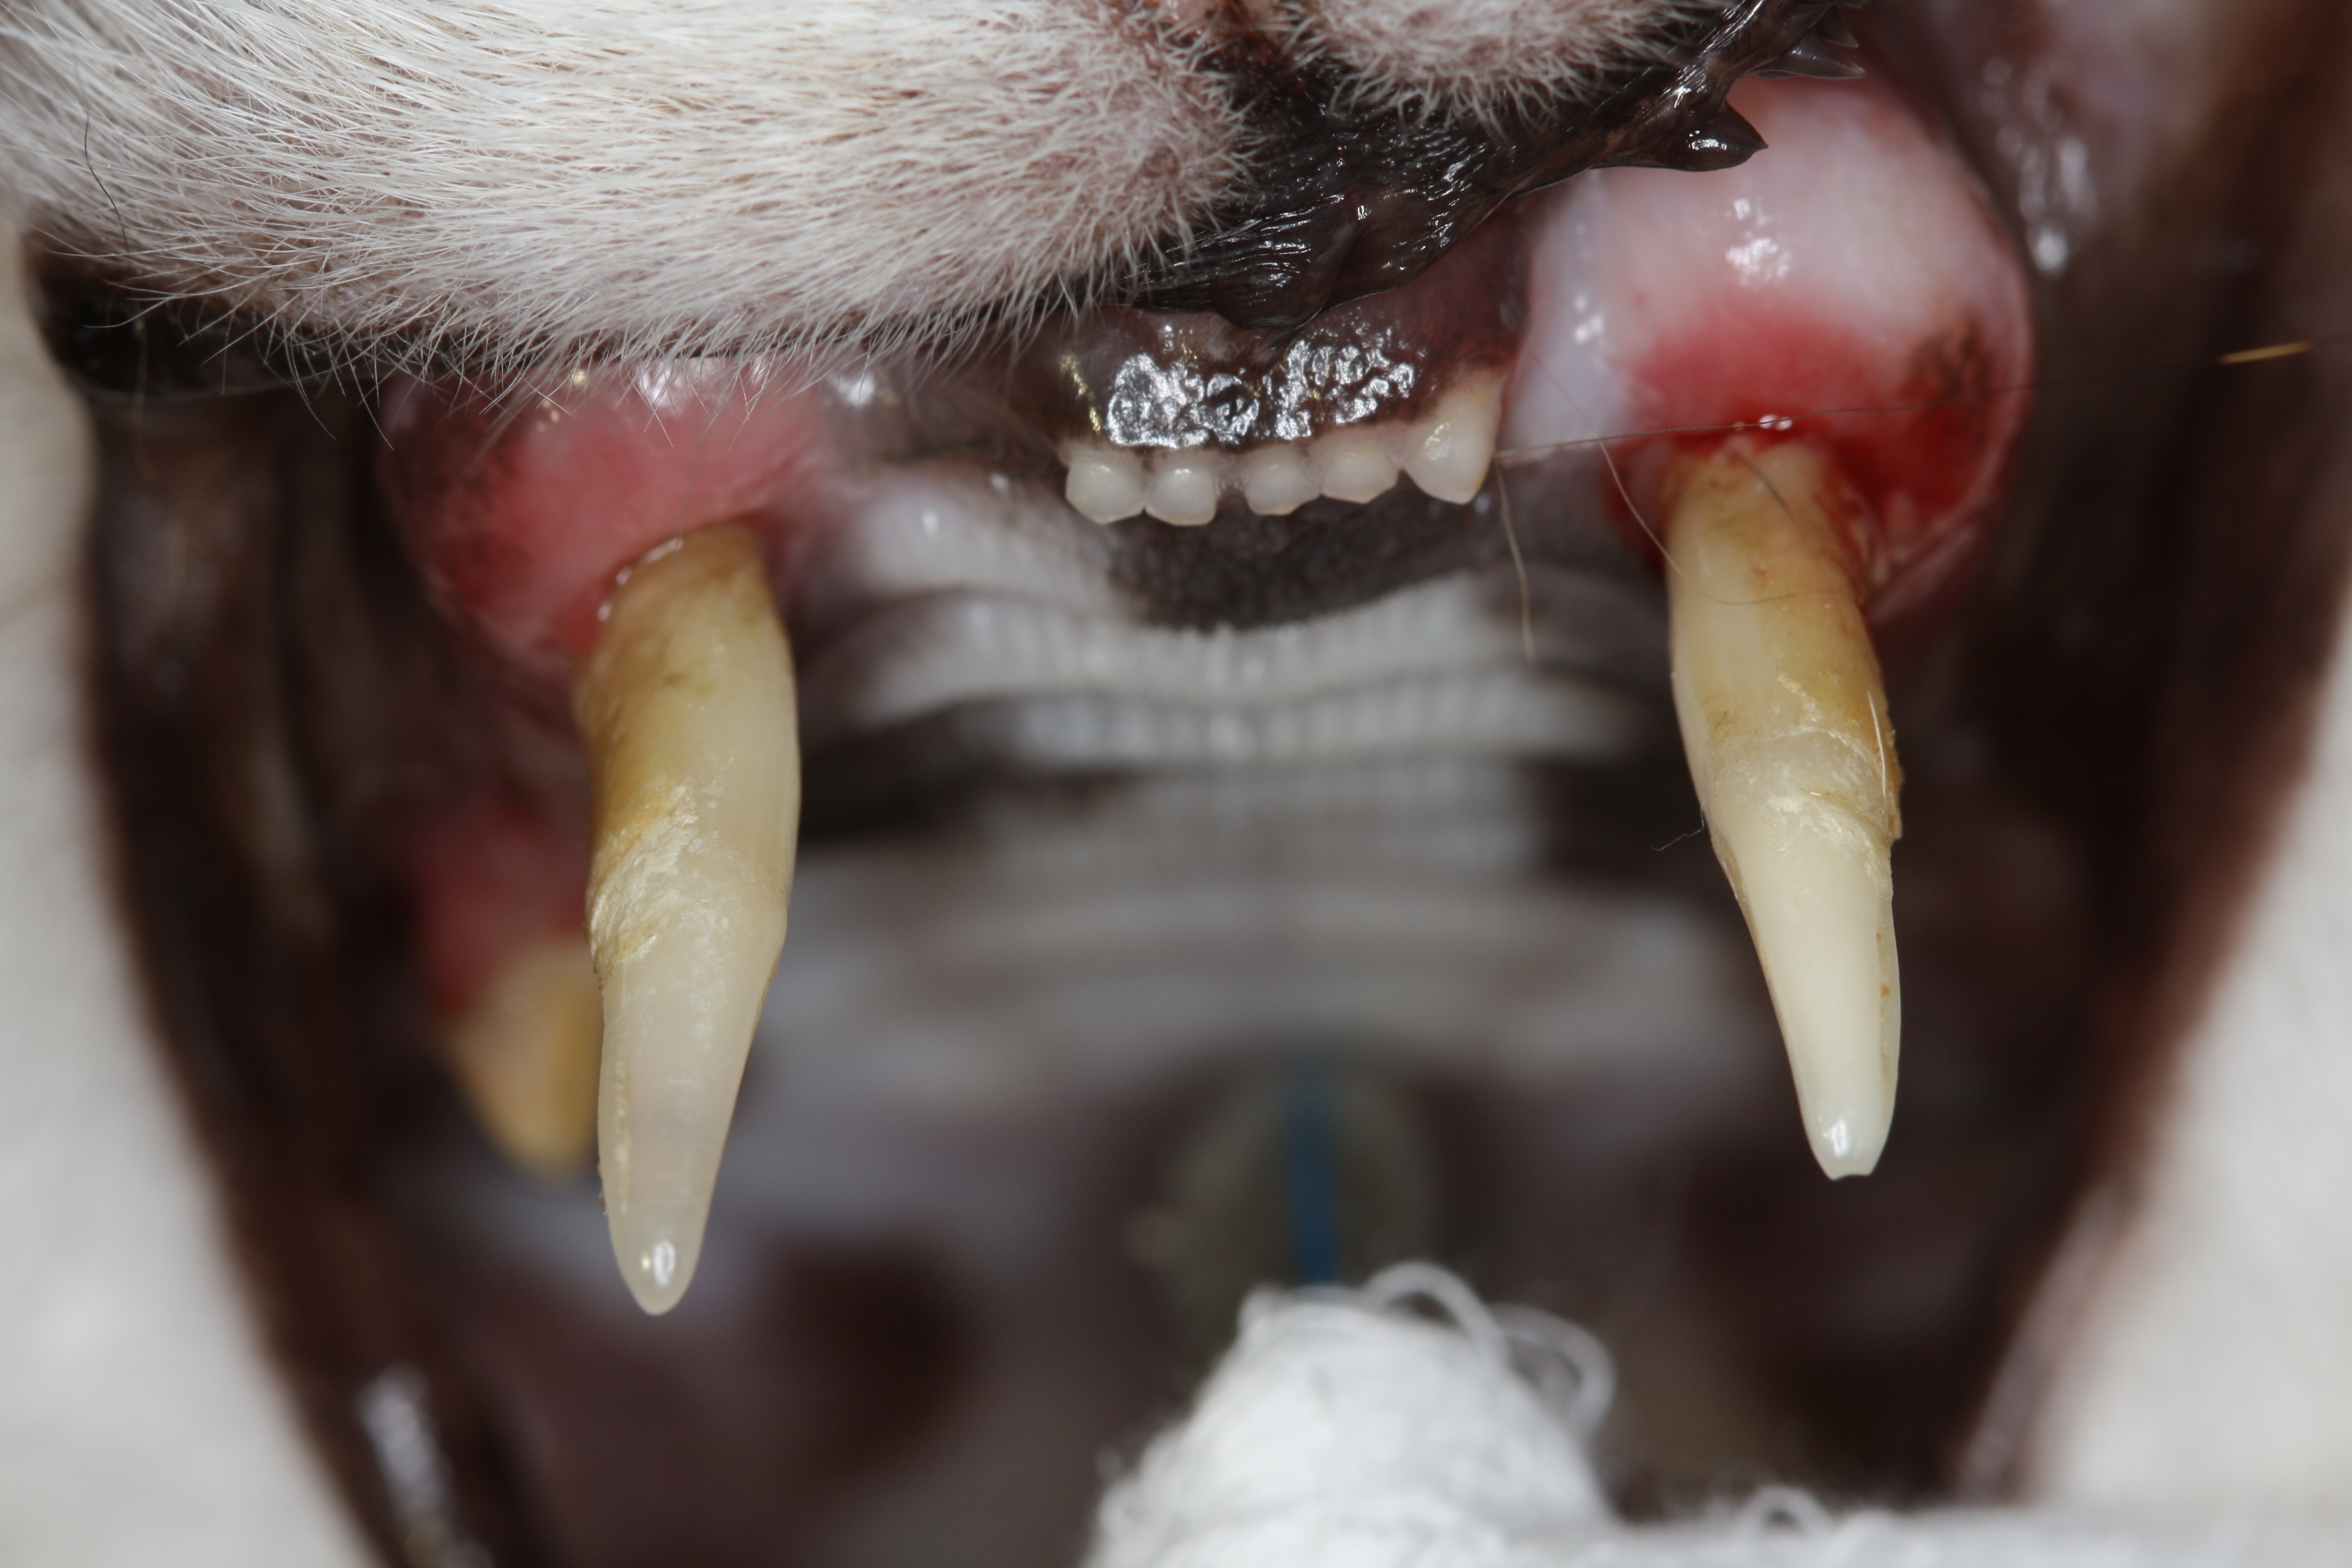

Die tägliche Erfahrung hilft uns dann, die richtigen Entscheidungen zu treffen. Zweifelsohne ist bei der Katze die komplette Dentalröntgenuntersuchung unverzichtbarer Teil einer fundierten Diagnosestellung geworden.

Ein Zahn mit einem grenzwertigen Befund wird beim geriatrischen Patienten möglicherweise eher gezogen als erhalten. Andererseits wird man sich beim älteren und beim Risikopatienten für eine möglichst unkomplizierte Vorgehensweise entscheiden. Sehr umfangreiche Operationen sollten im Interesse des Patienten möglicherweise auf mehrere Termine aufgeteilt werden. Somit ist ein besonderes Augenmerk auf ein gutes Zeitmanagement zu richten.